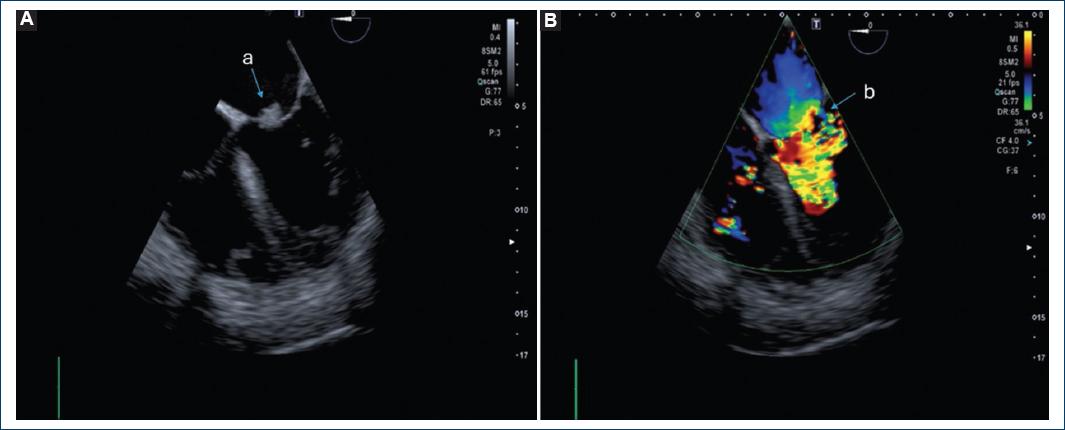

Blood cultures were performed with growth of Enterococcus faecalis, in addition to transthoracic echocardiogram showing large vegetation (area of 3.2 cm) with pedicle adhered to the non-coronary leaflet (Fig. 1), producing severe aortic regurgitation, moderate mitral regurgitation, severe tricuspid regurgitation (Fig. 2), so management with meropenem, vancomycin and gentamicin was indicated for 14 days. A transesophageal echocardiogram was performed, and a) vegetation in the anterior mitral leaflet of 14 mm in size with perforation of the leaflet with aortomitral continuity (Figs. 2A and B).

Figure 2 A: vegetation on the anterior mitral leaflet, 14 mm in size. B: perforation of the leaflet with aortomitral continuity.